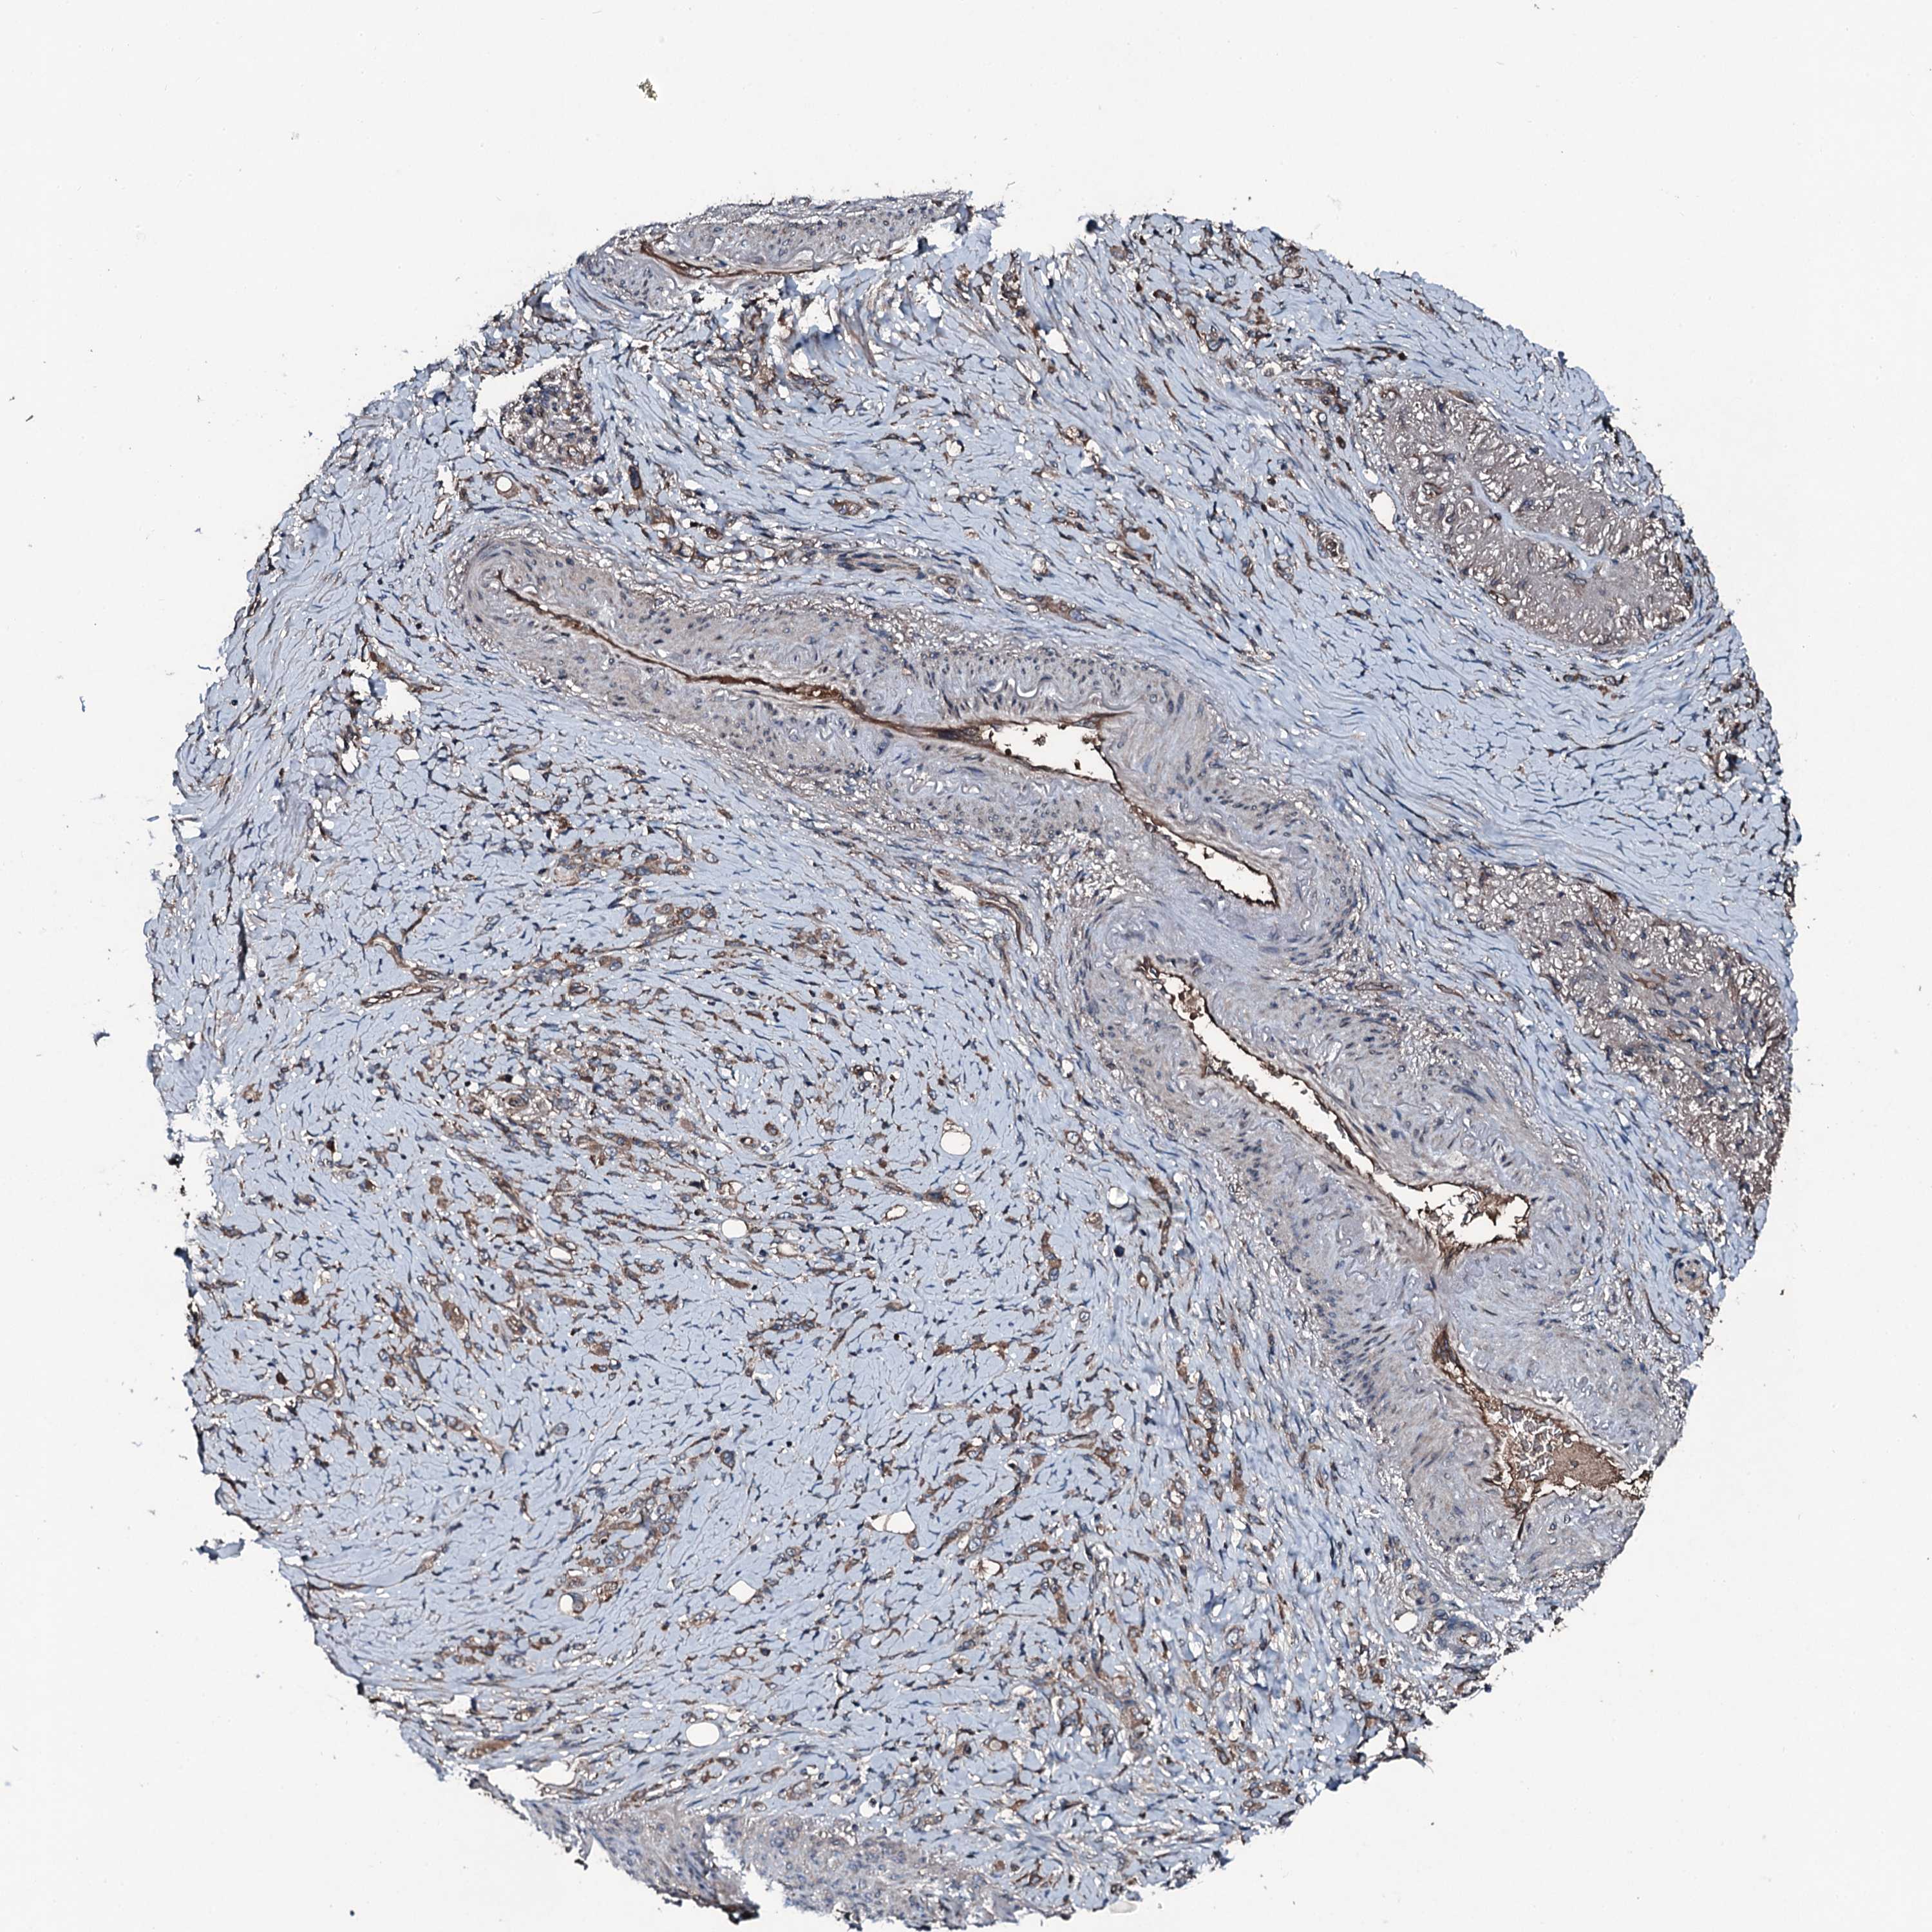

STOMACH CANCER - Protein expressioni

A mouse-over function shows sample information and annotation data. Click on an image to view it in a full screen mode. Samples can be filtered based on level of antibody staining by selecting one or several of the following categories: high, medium, low and not detected. The assay and annotation is described here.

Note that samples used for immunohistochemistry by the Human Protein Atlas do not correspond to samples in the TCGA dataset.

Antibody stainingi

Antibody staining in the annotated cell types in the current human tissue is reported as not detected, low, medium, or high, based on conventional immunohistochemistry profiling in selected tissues. This score is based on the combination of the staining intensity and fraction of stained cells.

Each image is clickable and will lead to virtual microscopy that enables deeper exploration of all samples and also displays staining intensity scores, fraction scores and subcellular localization as well as patient and tissue information for each sample.

Antibody CAB034261

Staining

High

Medium

Low

Not detected

Intensity

Strong

Moderate

Weak

Negative

Quantity

>75%

75%-25%

<25%

None

Location

Nuclear

Cytoplasmic/membranous

Cytoplasmic/membranous,nuclear

Adenocarcinoma, NOS

Adenocarcinoma, High grade